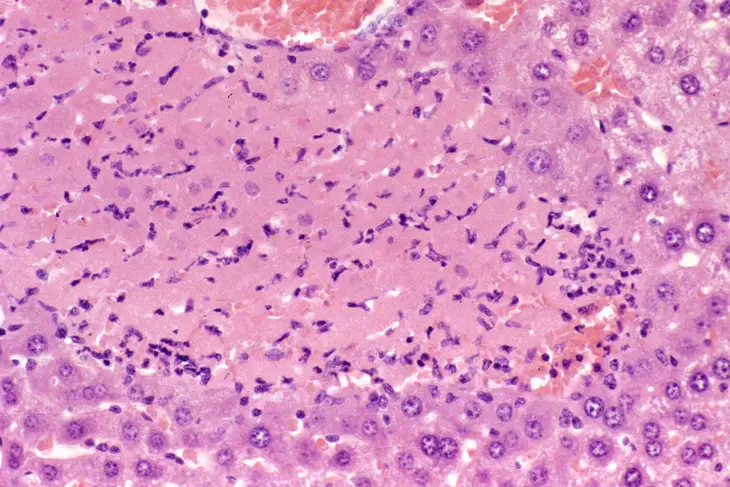

This is an example of centrilobular hepatocellular necrosis with associated hemorrhage sometimes referred to as hemorrhagic necrosis.